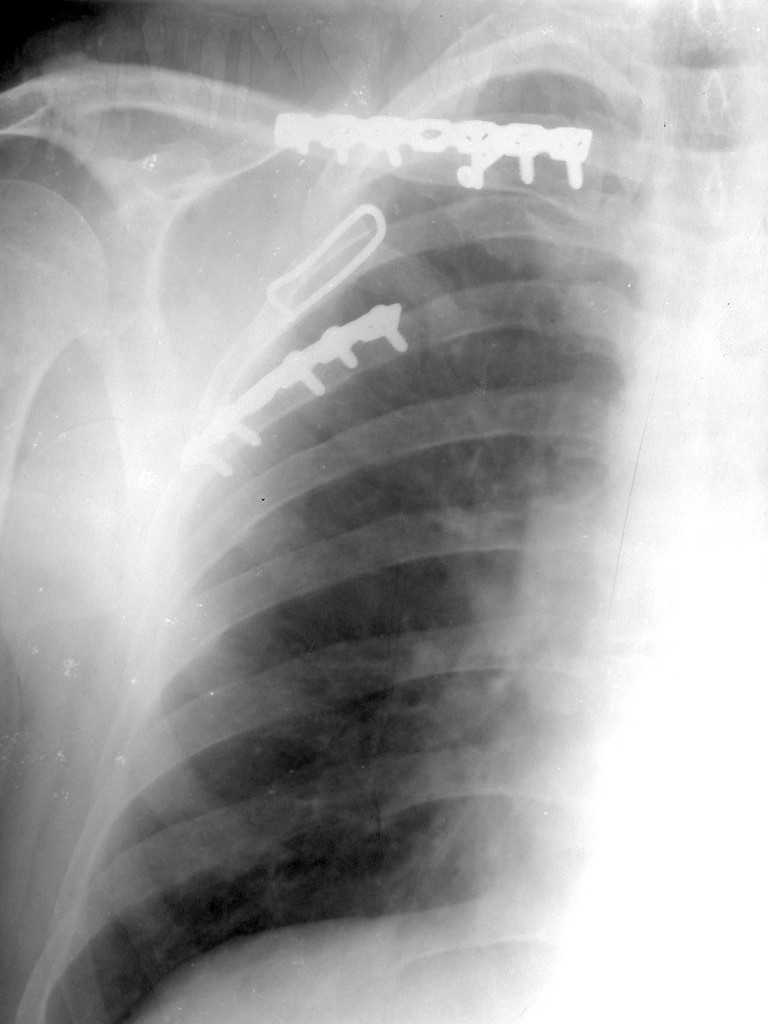

1. Стабилизация грудной клетки(фиксируем ребра по одной из линий рекон. LCP)

Всё зависит от типа нестабильности грудной клетки. Стабилизация проводится от 4 по 8 активно участвующих в дыхании рёбер. Т.е если имеется "створка" фиксируютс рёбра по одноё линии. Разрез продольный по линии переломов из которого фиксируются 2-3 ребра, если имеется "клапан", то фиксируютяс 2-3ребра по одной линии и 2-3ребра по другой линии. Репозиция несложная, фиксация реконструктивной пластиной, в хрящевой части лучше LCP.